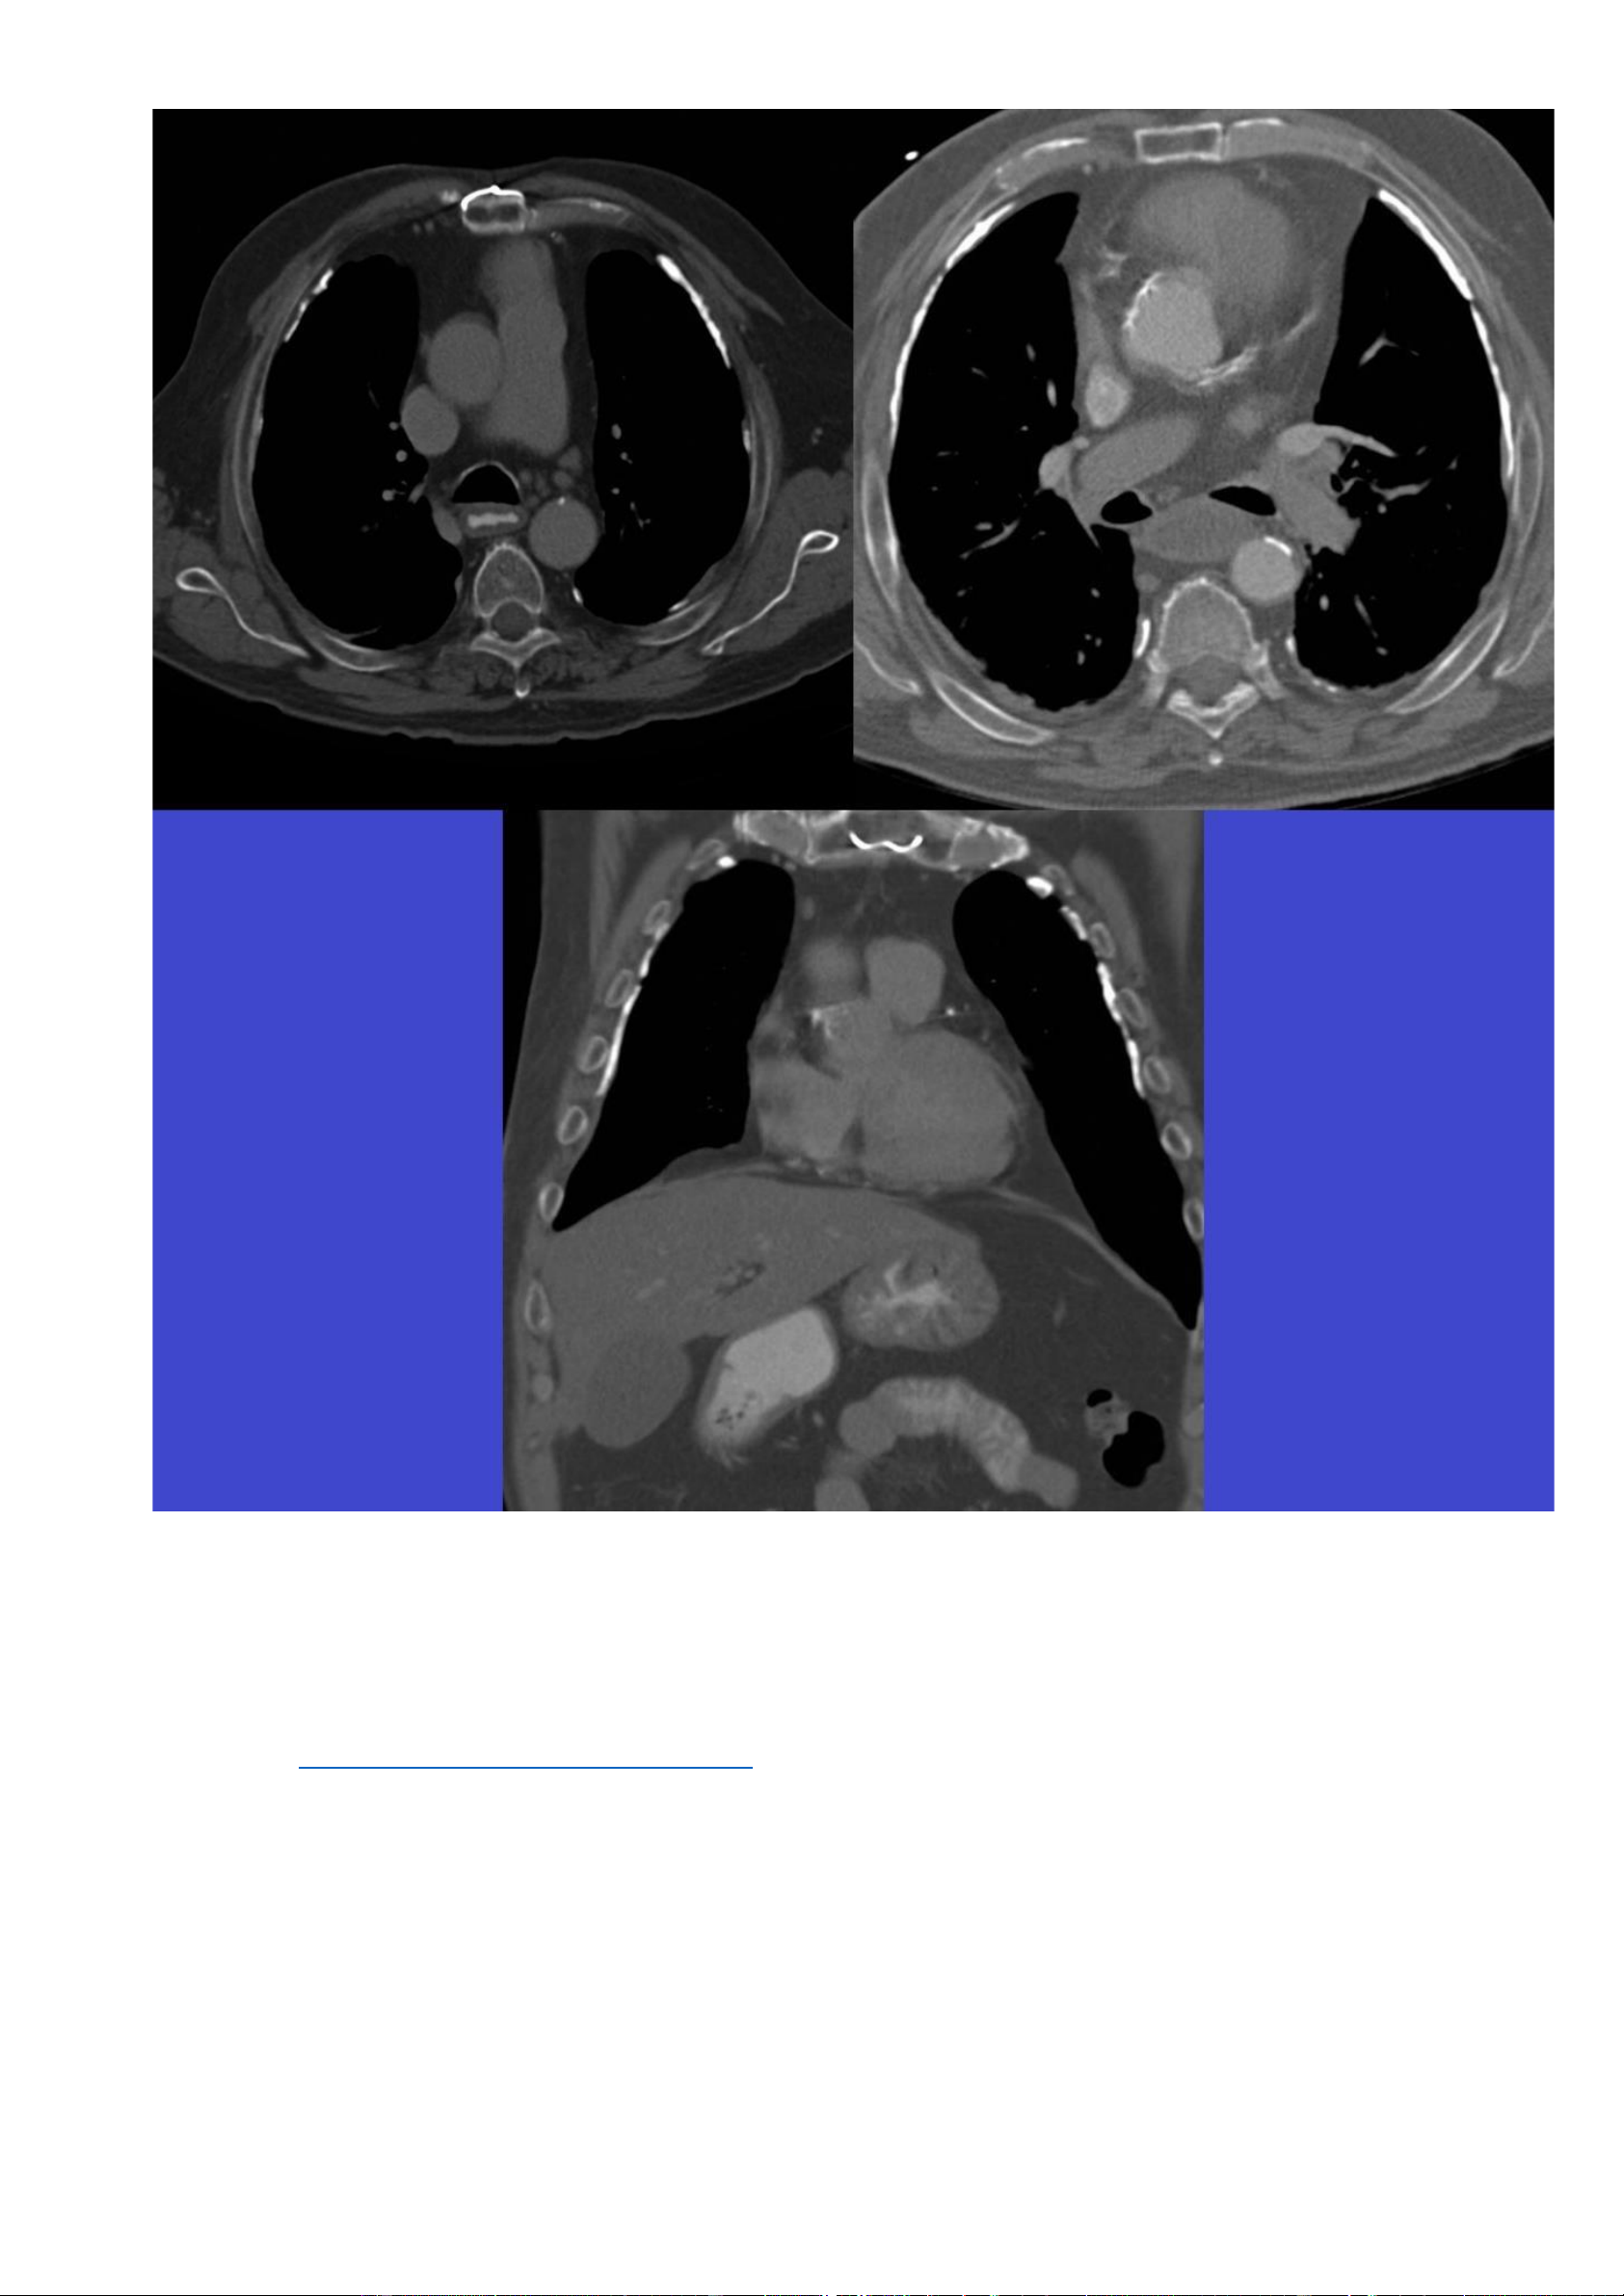

Hình ảnh CT (cửa sổ xương): lOMoAR cPSD| 22014077 Phan Tùng Bách

Các hình ảnh CT được lựa chọn cho thấy sự hiện diện của các màng màng phổi vôi hoá, đặc biệt là ở phần

trước-ngoài của màng phổi thành. Một vài mảng màng phổi không vôi hoá ở phần sau. Màng phổi trung thất và

các góc sườn hoành bình thường. 7.2. Trường hợp 2: -